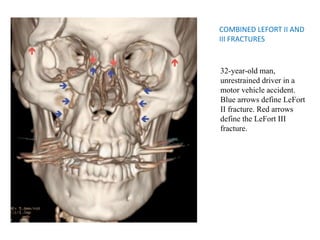

COMBINED LEFORT II AND

III FRACTURES

32-year-old man,

unrestrained driver in a

motor vehicle accident.

Blue arrows define LeFort

II fracture. Red arrows

define the LeFort III

fracture.